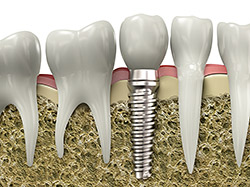

An implant is a synthetic tooth root in the shape of a post that is surgically placed into the jawbone. The “root” is usually made of titanium (the same material used in many replacement hips and knees), a metal that is well-suited to pairing with human bone. A replacement tooth is then fixed to the post. The tooth can be either permanently attached or removable. Permanent teeth are more stable and feel more like natural teeth.